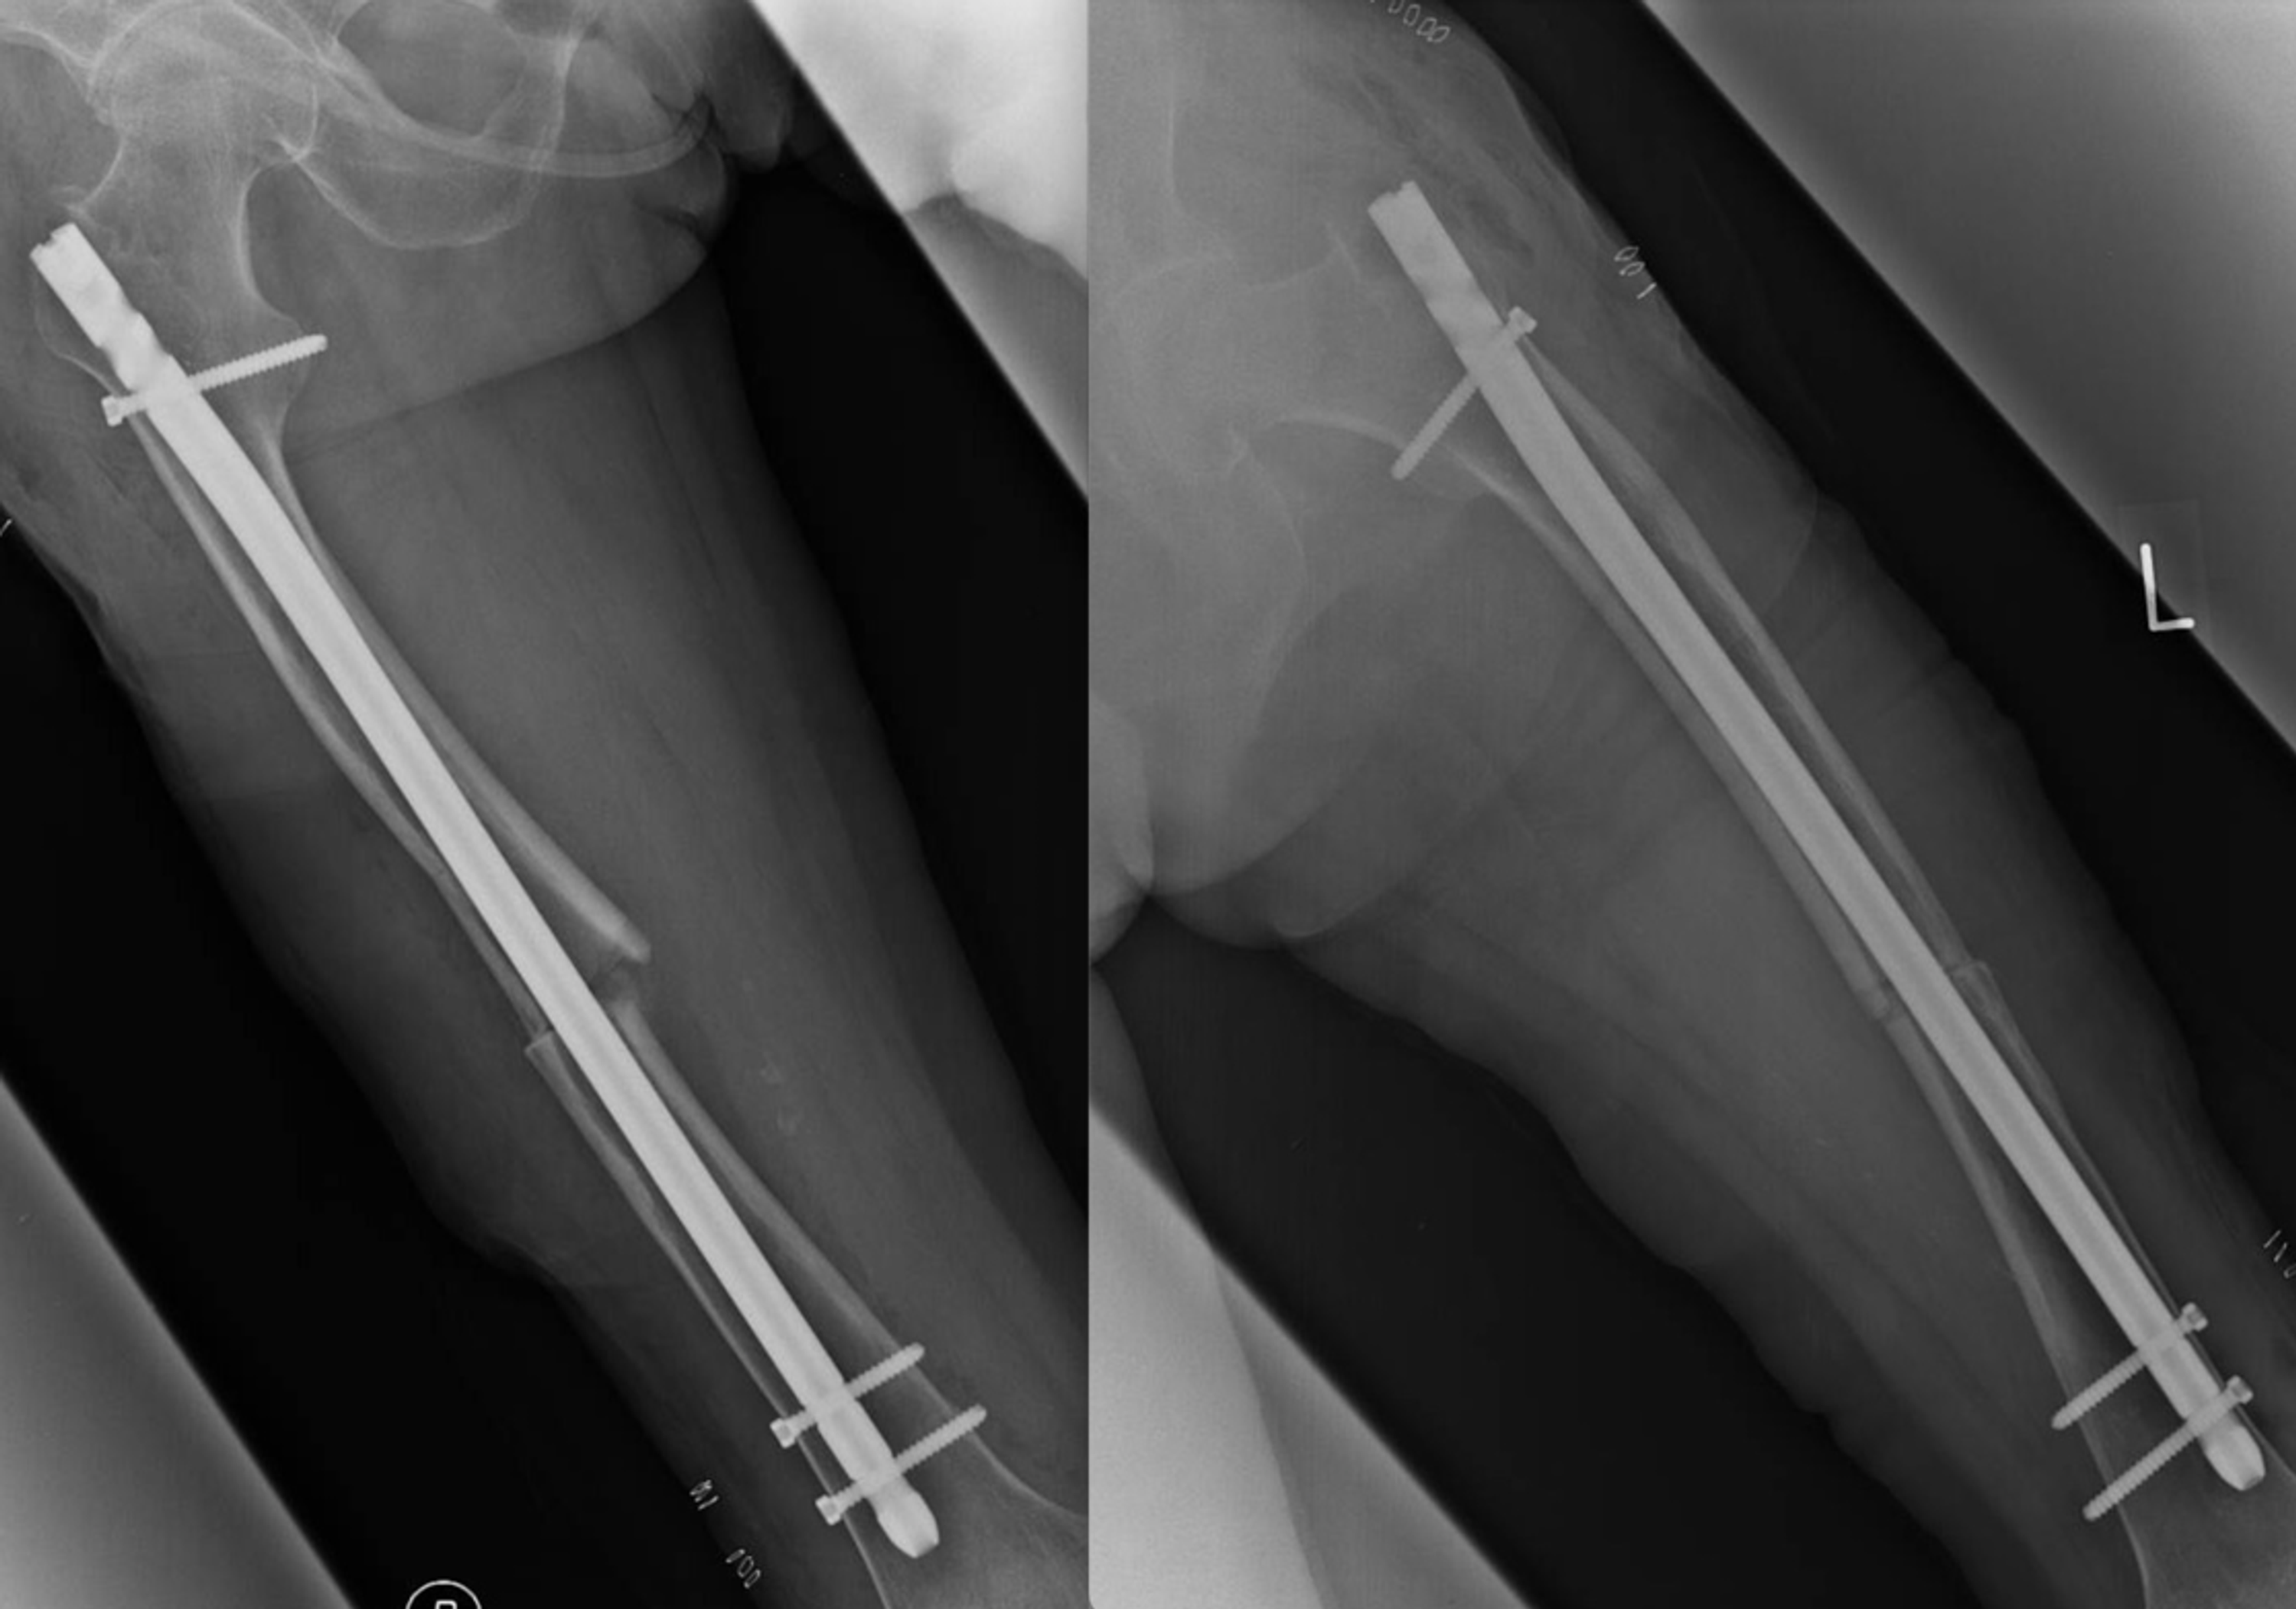

(a) Atypical left femur fracture sustained after a fall from standing

(a) Atypical left femur fracture sustained after a fall from standing Starting Bisphosphonate After Fracture early administration of bisphosphonates (bps) after surgery did not appear to delay fracture healing time either radiologically. upper gastrointestinal adverse effects, such as dyspepsia or reflux — these are common in the first month of treatment and often. osteoporosis is caused by the cumulative effect of bone resorption in excess of bone formation. eriksen et al.. Starting Bisphosphonate After Fracture.